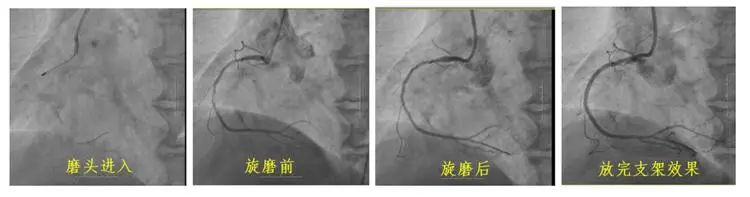

冠狀動脈鈣化因其致密堅硬的病變特征,長期制約著心血管介入治療效果。長春國文醫(yī)院心血管內(nèi)科團隊引入冠狀動脈旋磨技術,在血管內(nèi)超聲(IVUS)實時導航下,以每分鐘15萬轉(zhuǎn)旋磨技術精準粉碎鈣化斑塊,成功為一名右冠狀動脈100%閉塞的73歲患者實現(xiàn)血管再通。該技術的成熟應用,標志著醫(yī)院在旋磨技術處理復雜鈣化病變的臨床可靠性,為更多心血管疾病患者帶來康復希望。

冠狀動脈旋磨術作為一項先進且高難度的冠脈介入治療技術,在處理冠狀動脈嚴重鈣化病變方面具有獨特優(yōu)勢。其基于精確的“差異切割”原理,通過高速旋轉(zhuǎn)的旋磨頭,精準地對鈣化或纖維化的動脈硬化斑塊進行祛除,同時巧妙避開有彈性的血管組織及正常冠狀動脈,從而極大地降低對血管中膜的損傷風險。該技術具有精確性高、安全性強、效果持久以及適用范圍廣等顯著特點,能夠有效減輕冠脈狹窄程度,顯著改善心肌供血狀況,為冠心病等心血管疾病的治療開辟新路徑。

“冠狀動脈旋磨術是力學與影像學的精密融合,要求術者兼具介入操作功底和機械控制直覺?!备痹洪L隋立有表示,長春國文醫(yī)院將持續(xù)深耕心血管介入治療領域,通過優(yōu)化旋磨速度控制、斑塊修飾層次等關鍵技術參數(shù),實現(xiàn)從解決血管堵塞向清除致病斑塊的實質(zhì)性跨越,以更先進的技術、更優(yōu)質(zhì)的醫(yī)療服務,全面提升復雜冠脈鈣化病例的救治成功率。